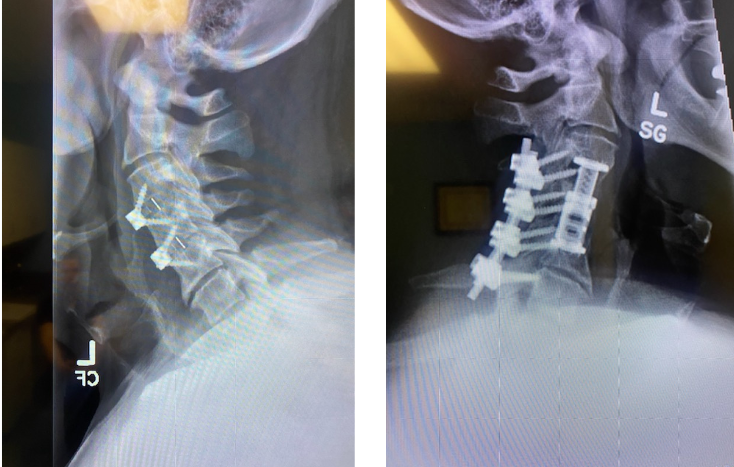

Javier's spine before (left) and after (after) treatment from Dr. Verma

“We created an incision in his neck to reach the faulty implants,” said Dr. Verma. “We drilled into the bone, took out his old implants and put in a new plastic cage and screws to take pressure off the nerves in his neck.”